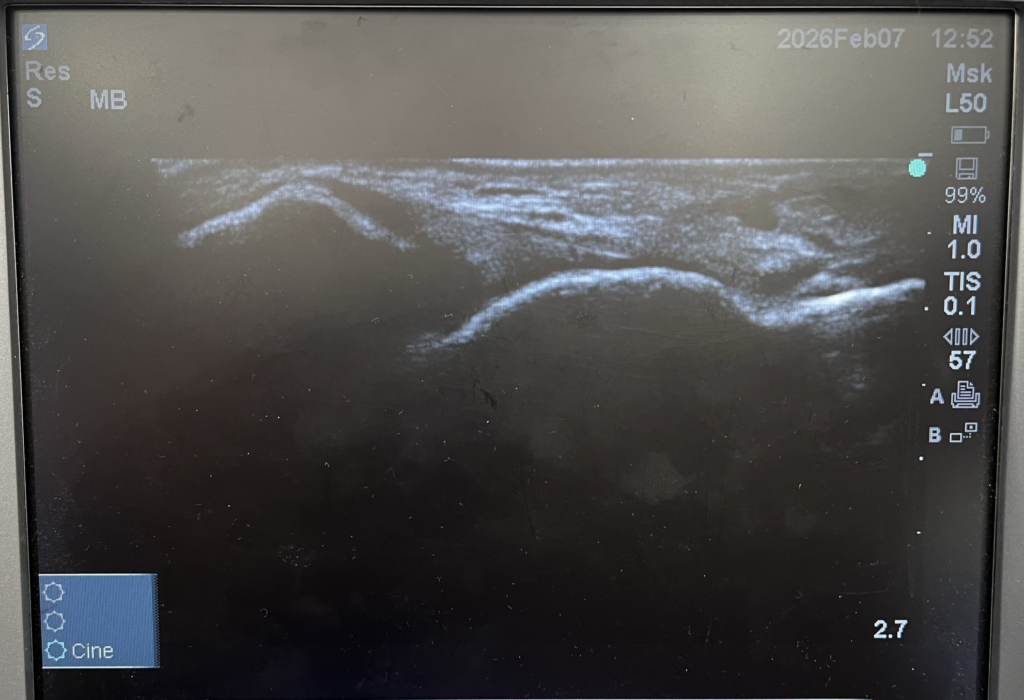

エコー検査が捉えた足首の腫れと靭帯損傷

おりおスポーツ接骨院では、初回のカウンセリング時に超音波エコー検査を実施しています。エコー検査は、超音波を使って体内の軟部組織をリアルタイムで観察できる検査方法です。レントゲンでは見えない筋肉、靭帯、腱、神経などの状態を詳しく確認することができます。

S様のエコー検査では、右足首の外側靭帯周辺に明らかな腫れが確認されました。左足と比較すると、腫れている部分の組織が黒く映り、正常な組織とは明らかに異なる状態でした。また、靭帯に触れると痛みがあり、まだ治癒途中であることが分かりました。

さらに、外くるぶしの近くに骨の一部が剥がれたような影が見られ、剥離骨折の可能性も示唆されました。これは、靭帯が強く引っ張られた際に、靭帯の付着部の骨が一緒に剥がれてしまう怪我です。剥離骨折は、レントゲンでも見つけにくいことがあり、特に子どもの場合は骨が柔らかいため、エコー検査でないと発見できないこともあります。

エコー検査のメリットと重要性

超音波エコー検査には、以下のようなメリットがあります。

リアルタイムで観察できる

エコー検査は、画像をリアルタイムで確認しながら行えるため、関節を動かしながら靭帯や筋肉の動きを観察することができます。これにより、静止画では分からない動的な問題も発見できます。

放射線被曝がない

レントゲンやCTと異なり、エコー検査は放射線を使用しないため、成長期の子どもにも安心して繰り返し検査を行うことができます。治療の経過を追うためにも、定期的にエコー検査を行うことで、回復状況を正確に把握できます。

痛みの原因を視覚的に説明できる

エコー画像を見ながら説明を受けることで、保護者の方もお子さん自身も、どこがどのように傷んでいるのかを理解しやすくなります。目で見て確認できることで、治療への納得感や安心感が高まります。

北九州市八幡西区や折尾周辺で、超音波エコー検査を導入している接骨院は限られています。おりおスポーツ接骨院では、最新のエコー機器を導入し、的確な診断と治療計画の立案に役立てています。